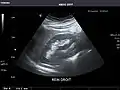

Right kidney